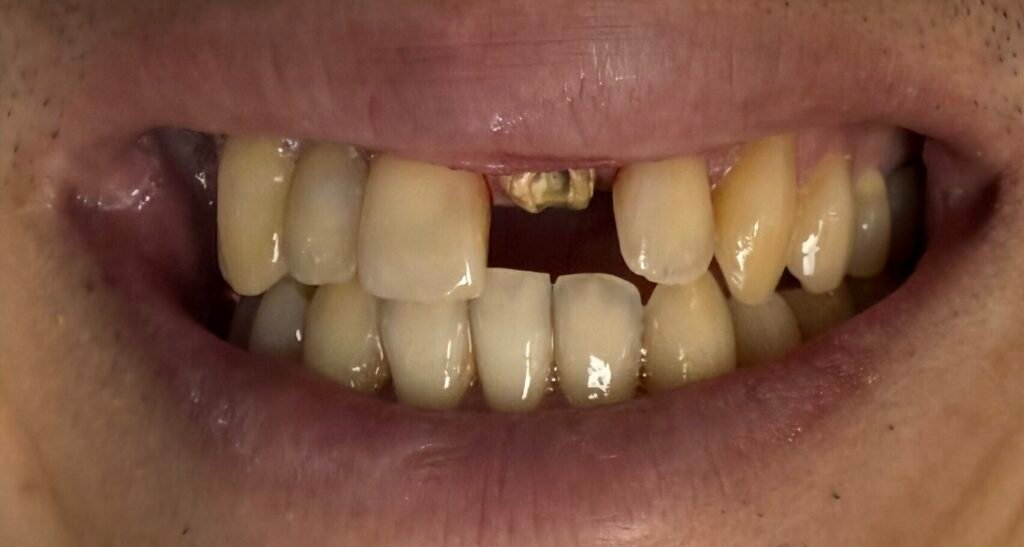

Periodontal diseases are infections of the gums that gradually destroy the support system of your natural teeth. It is a startling fact that adults over 35 lose more teeth to gum disease than to cavities, with three out of four adults affected at some point in their lives. At Huh Dental Wellness in Sunnyvale, we focus on early diagnosis and proactive gum treatment to preserve your smile for a lifetime.

Understanding the Plaque Factor